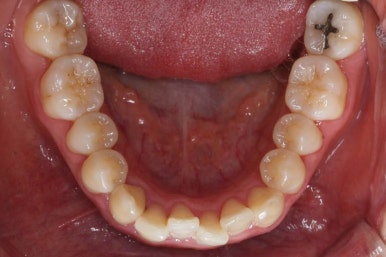

마찬가지로 부산설측교정 키다리아저씨치과에서 처음 내원하셨을 당시의 입안 모습입니다.

어금니쪽은 특별히 이상이 없었고, 위아래 앞니만 삐뚤한 상태였습니다.

이번 환자분은 앞니쪽의 삐뚤한 것만 개선되면 되었기 때문에 부분교정으로 하기로 하였습니다.

부분교정 때 중요한 것은 어금니에는 장치를 부착하지 않고 움직이지 않기 때문에 부분교정으로 개선할 수 없는 경우도 있을 수 있습니다.